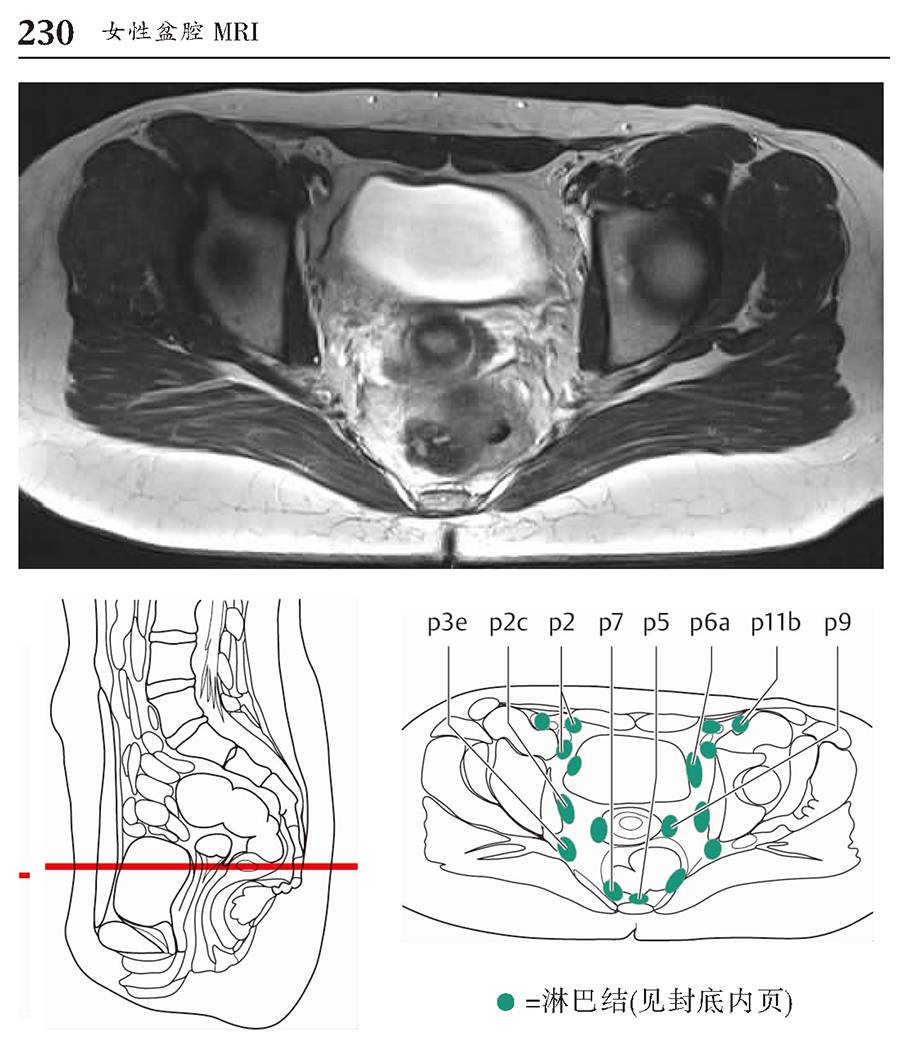

本书为断层解剖图谱,包括头颈部断层解剖,还包括脑部血管造影术,每一层面都包括精确的断层解剖和对应的彩色插图,左边页面为CT/MR图像,右边页面为对应的彩色手绘解剖示意图,便于学习和记忆!

1、版面采用教学式设计,2页为一个单元,左边页面为CT/MR图像,右边页面为对应的彩色手绘解剖示意图,并一一注明了解剖部位。

3、彩色手绘示意图中,各断层图像中同一个解剖结构均采用相同的颜色标注,便于识别。

书中全面、详细描述了每个CT/MR断层的解剖部位,图片清晰,浅显易懂,非常便于阅读和理解。书中每幅CT/MR图像都配有手绘的彩色示意图,示意图与影像图片高度匹配,通过示意图可以加深对CT/MR图像的理解,使CT/MR图像不再那么抽象难懂,同时也增加了学习的乐趣,不再感觉CT/MR图像的学习非常枯燥。本书内容全面、简洁易懂,是一本高质量的解剖图谱,非常适合影像诊断专业医师学习。

版面采用 教学式设计,2页为一个单元,左边页面为CT/MR图像,右边页面为对应的彩色手绘解剖示意图,并一一注明了解剖部位。

彩色手绘示意图中,各断层图像中同一个解剖结构均采用相同的颜色标注,便于识别。

女性盆腔MRI-横断面